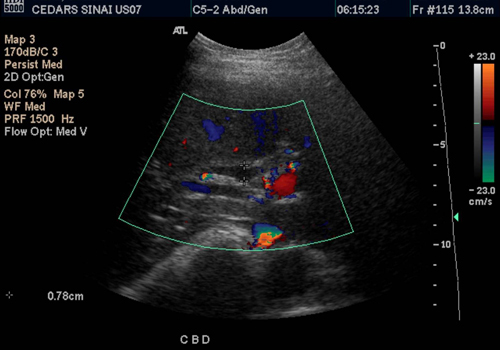

Whole Ab Scan

An abdominal ultrasound is a safe and painless test that uses sound waves to make images of the abdomen (belly). During the examination, an ultrasound machine sends sound waves into the abdominal area and images are recorded on a computer. The black-and-white images show the internal structures of the abdomen, such as the appendix, intestines, liver, gall bladder, pancreas, spleen, kidneys, and urinary bladder. A complete ultrasound of the abdomen evaluates all of the abdominal organs.